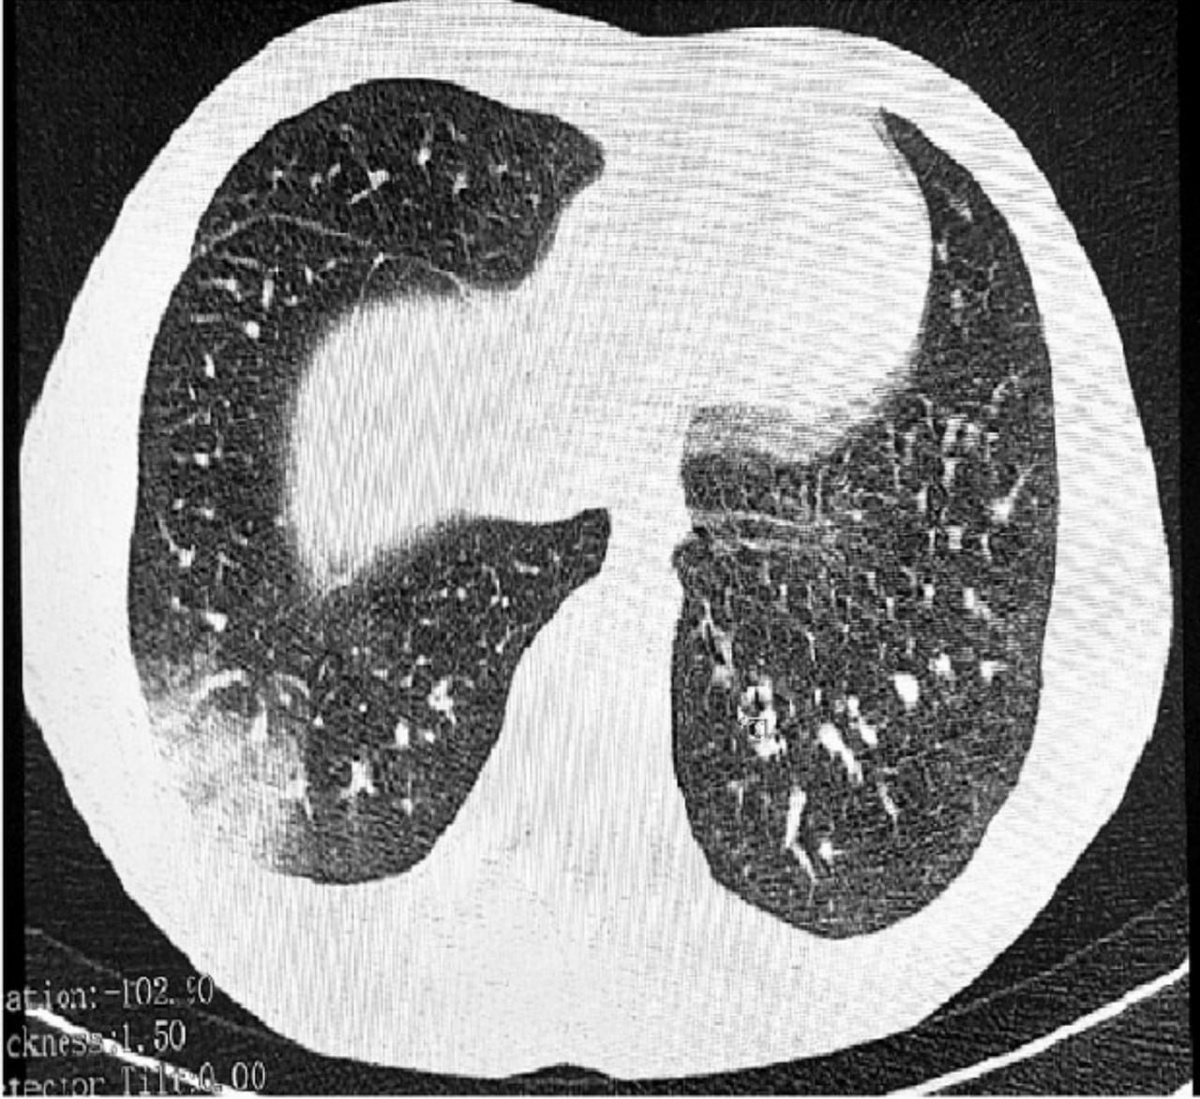

Да-да, вы не ослышались! 😲 У одного из них диагностировали дыхательную недостаточность, а у другого — двустороннюю пневмонию EVALI. Операция стала настоящим хитом для врачей! 🎭 Врачи, как настоящие герои, предупреждают: жидкости для вейпов — это не просто дым, а настоящая катастрофа для дыхательных путей. Так что, если вы думали, что вейп — это просто модный аксессуар, подумайте дважды!

В Ростовской области произошло нечто курьезное: троих подростков с "попкорновой болезнью" лёгких доставили в реанимацию. Да-да, вы не ослышались!

😲 У одного из них диагностировали дыхательную недостаточность, а у другого — двустороннюю пневмонию EVALI. Операция стала настоящим хитом для врачей!